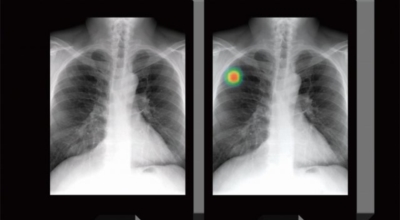

폐암 검사는 X-ray를 통해서 검사하는데 , 크기가 작거나 구석에 위치한 경우 확인이 어려운 경우도 있답니다. 그리고 조직 검사를 통해서 정확한 진단을 하게 되어요. 폐암이 발견되면 종양의 크기나 전이 여부 , 위치에 따라서 수술 여부를 결정하게 됩니다.